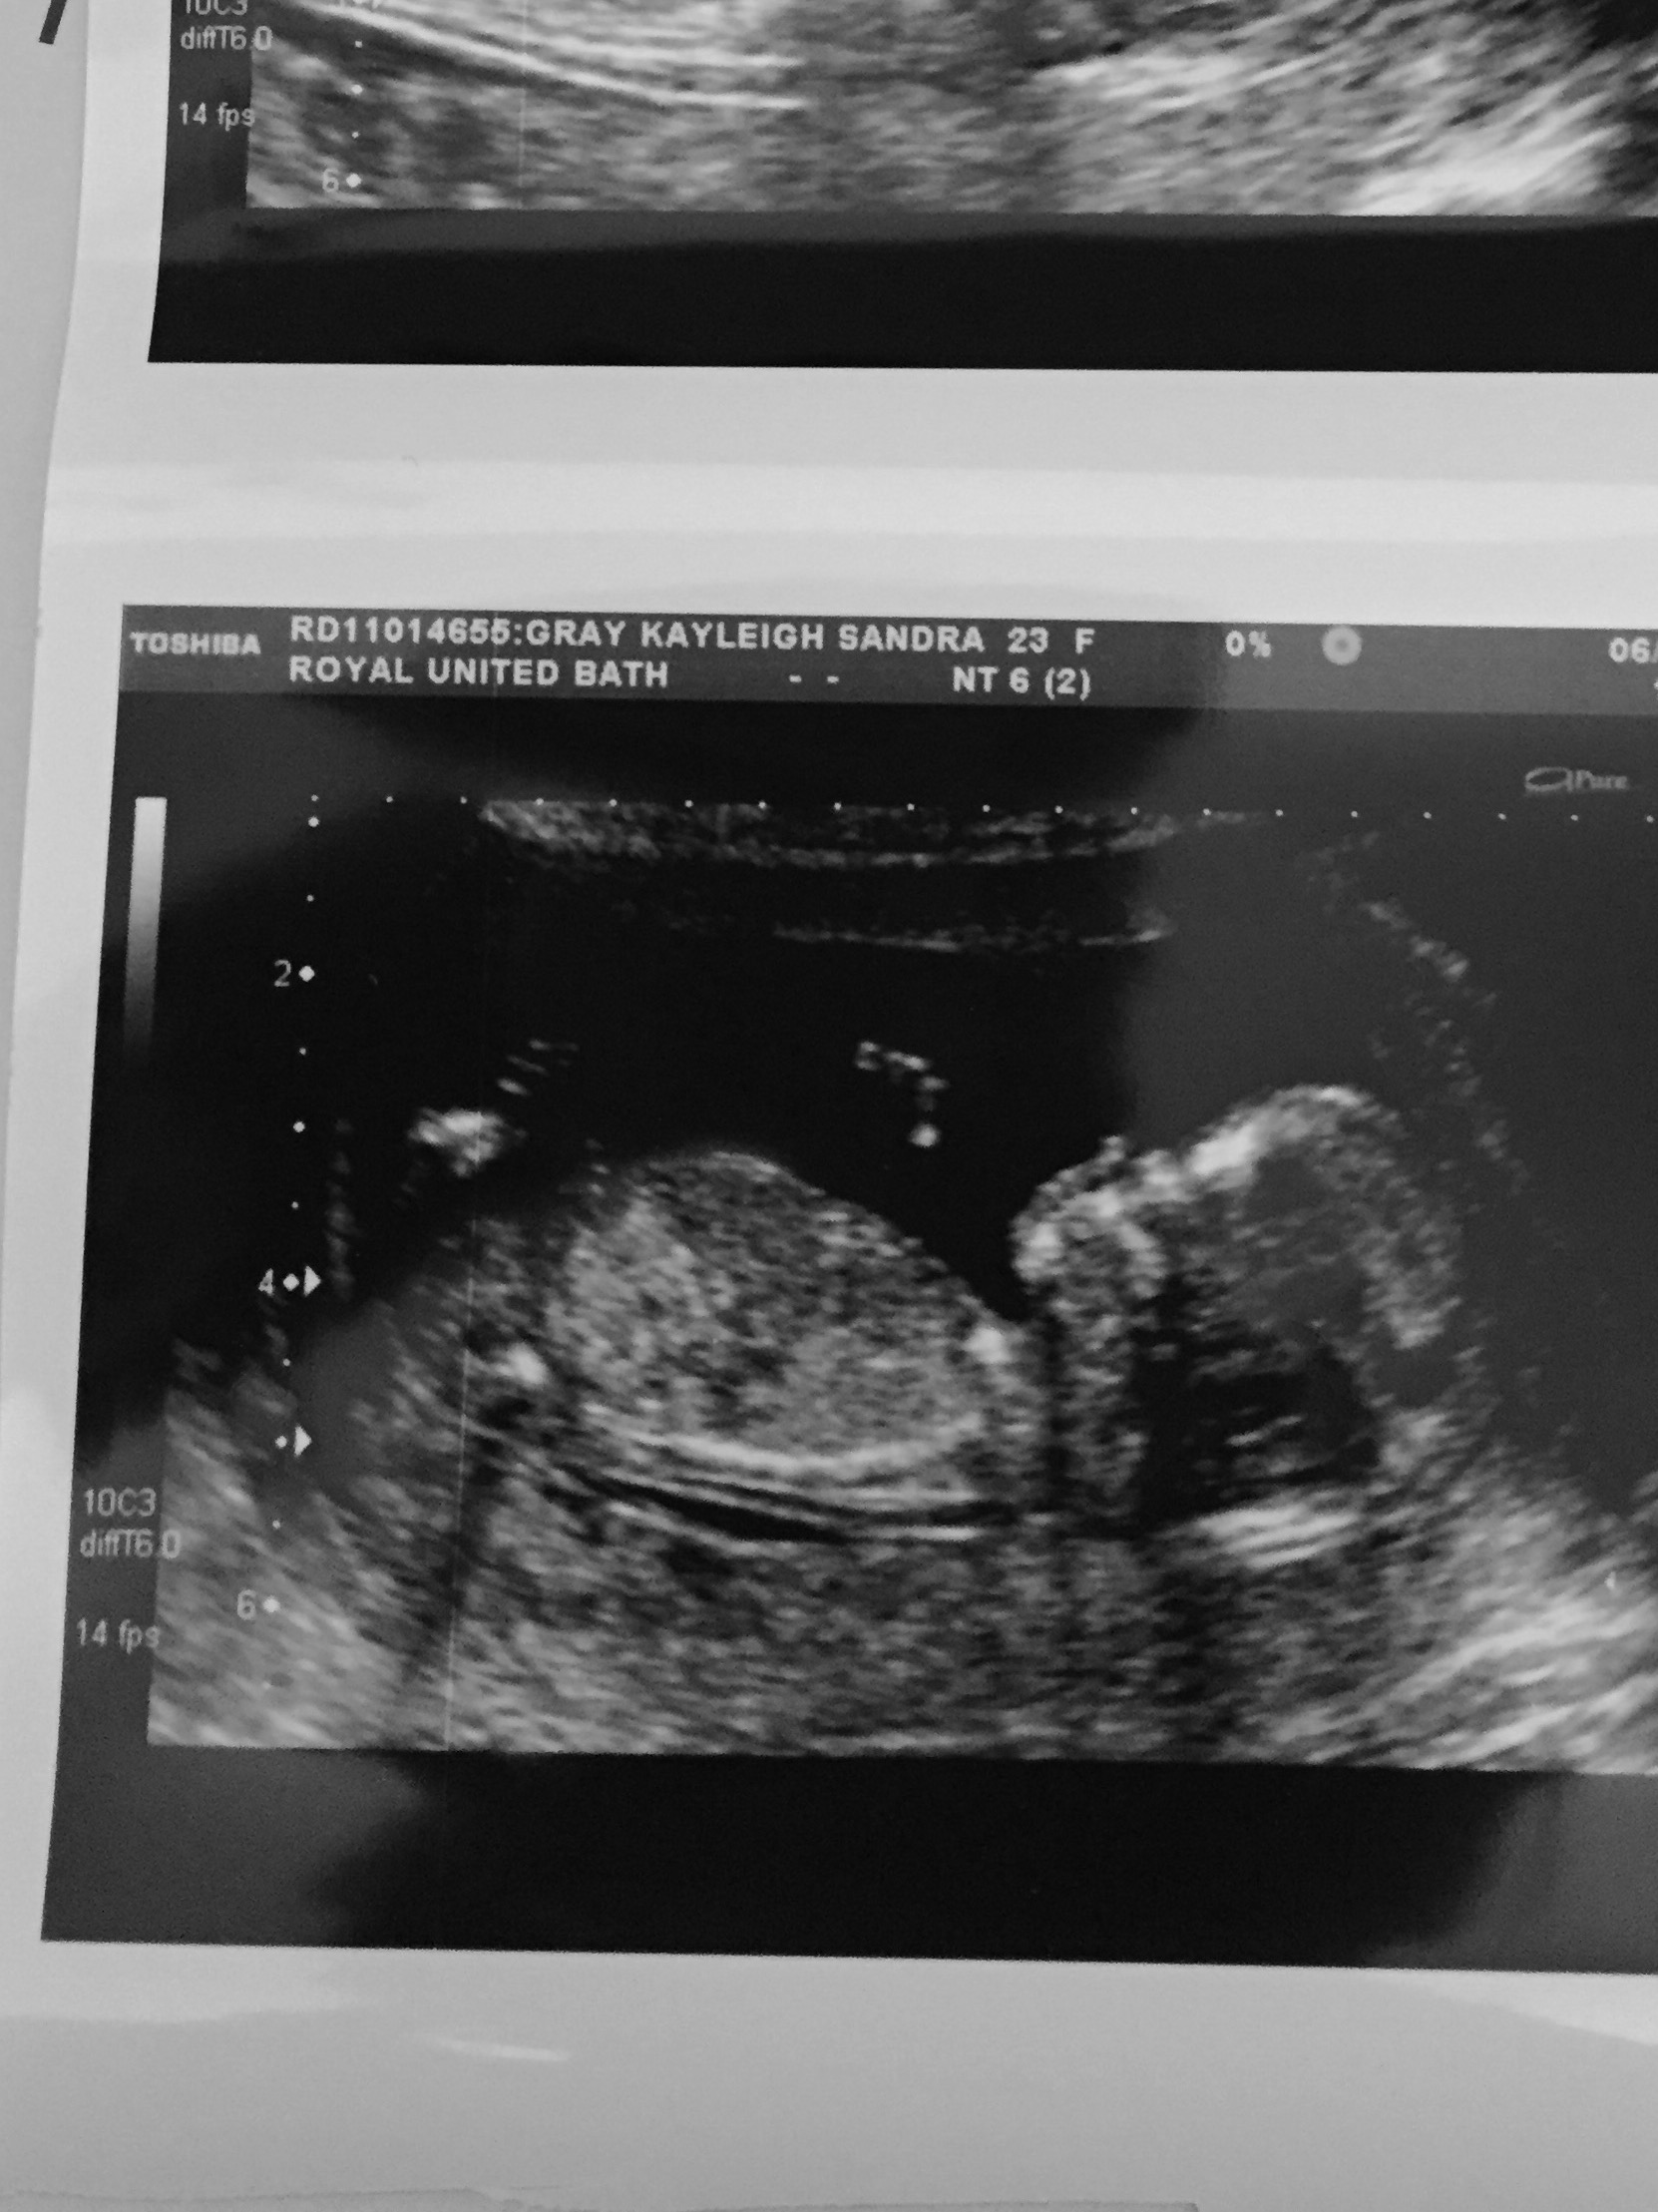

This scan was at 13 so the nub would of had time to rise, I no the nub hasn't been completely captured by going by this is the top line visible is it likely it could be a girl as there's no major boy bits? Thanks

I don't think this pic is clear enough to tell either way. Do you have another pic?

This is just too grainy and I do not see a clear nub.

No nub.